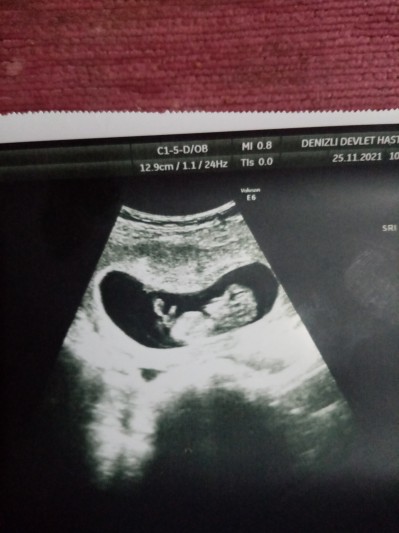

image

12.9 yazan yer ne oluyor boyumu bilen varsa yardımcı olabilir mi

Gebelik haftası 11.1

Baştan popo bitimine kesik kesik bir çizgi varsa o mesafenin ölçüsü olmali

11. Haftada kese boyutunuz 12.9 cm olamaz. 6 haftalıkken 20 cm falan oluyor çünkü. Bebeğin boyu da olamaz çünkü 11. Haftada 5 cm civarı oluyor. Başka bir şeydir.

Kese boyutu diye biliyorum çünkü bebegin boyu olsa fl yazması lazım